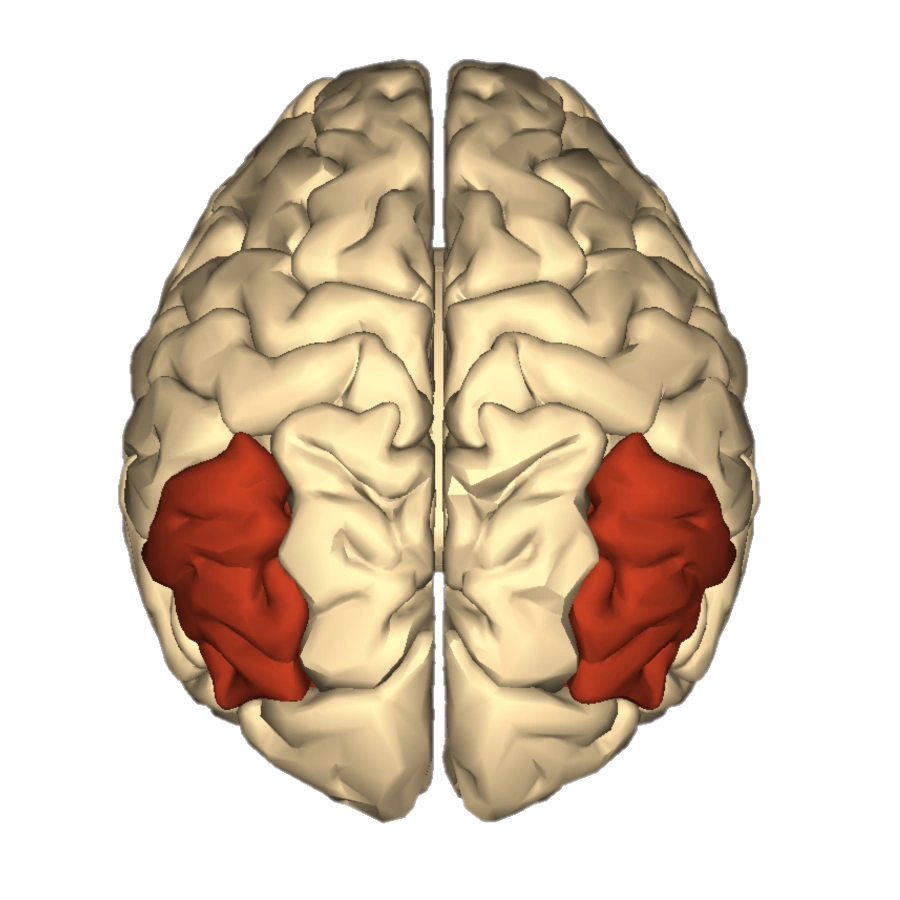

Супрамаргинальная извилина: Функции и Исследования